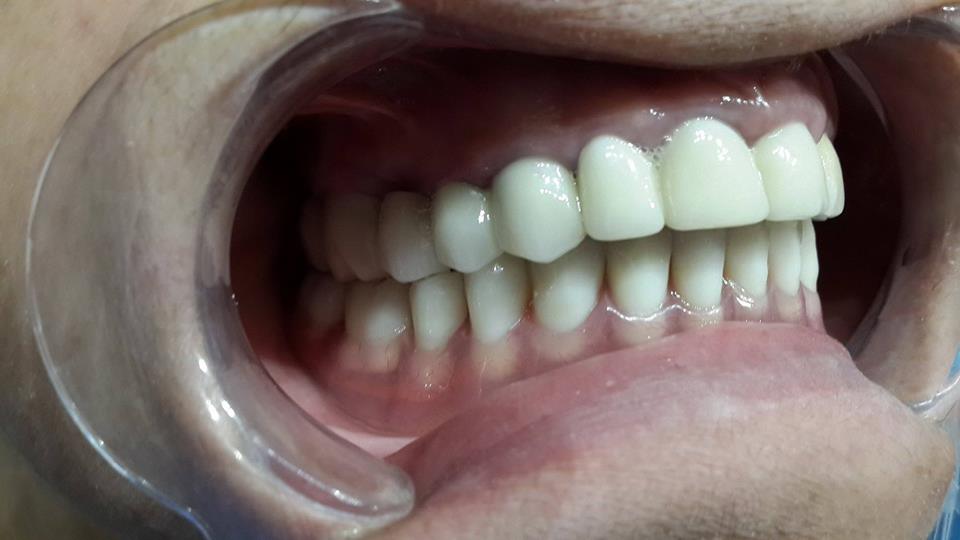

Prosthesis of the lower jaw on 4 implants

The patient was given a prosthetic lower jaw on 4 implants.